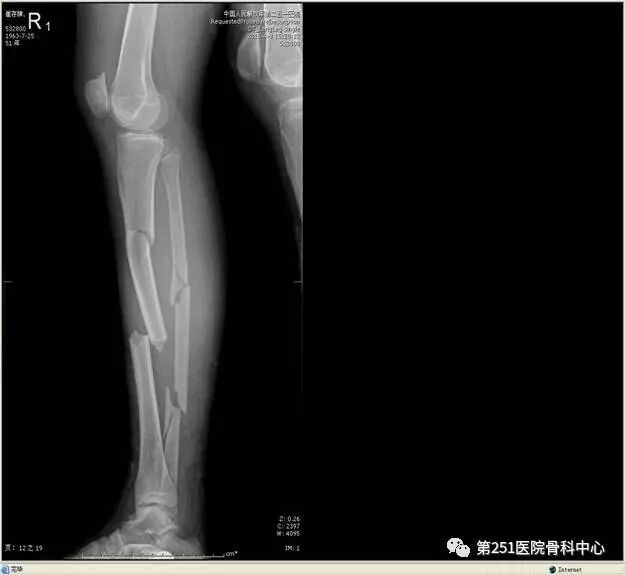

病例2:男性,44岁,车祸伤,双侧胫腓骨骨折(左侧)。

![]()